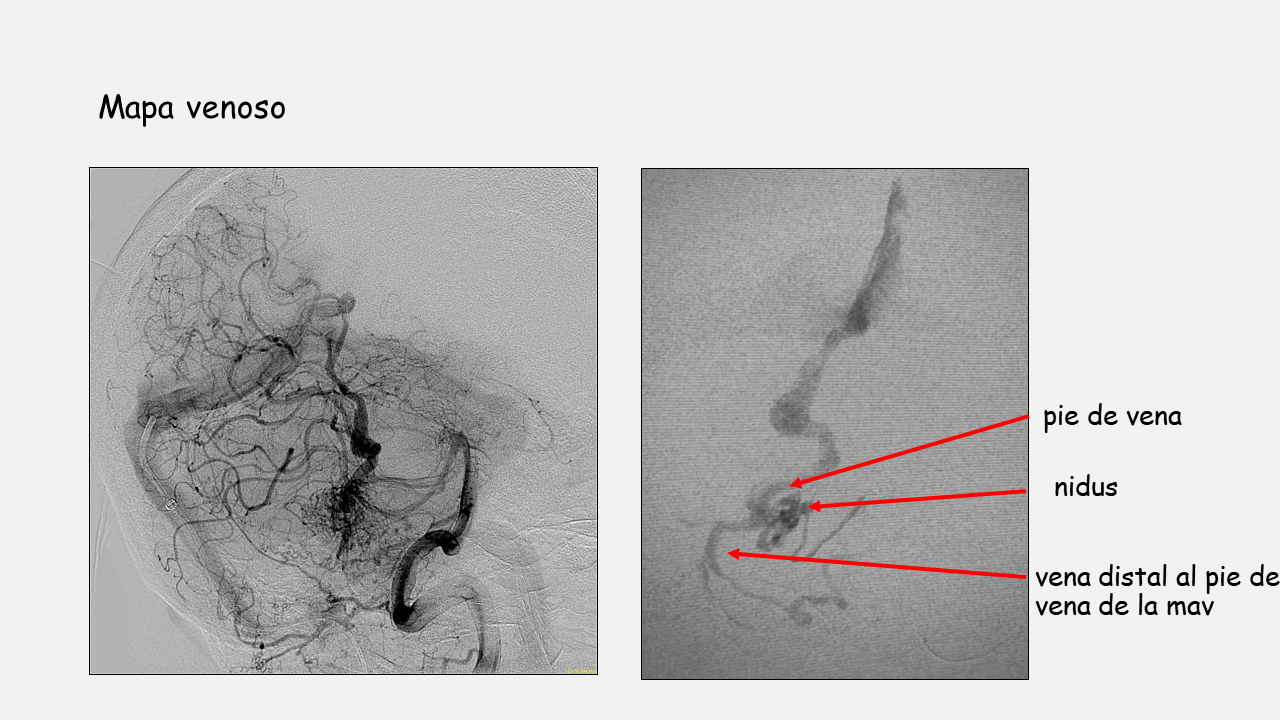

- Al presentar una vena de drenaje única se procede a la embolización vía venosa utilizando microcatéter con punta desprendible y técnica de olla a presión.

- El objetivo de la embolización es que el agente embolizante ocluya el pie de vena con el menor reflujo posible y penetre en el nidus y en la parte distal de los pedículos arteriales para evitar sangrados postembolización.

- El pie de vena no es ciego por lo que se emboliza su trayecto distal para evitar la progresión del agente embolizante hacia esa vena.

- Posteriormente se colocan coils en la parte proximal de la vena y se inicia la inyección de agente embolizante de mayor densidad (18) hasta que se rellena todo el pie de vena. En este momento se inyecta pegamento al 50% para sellar la zona venosa donde están los coils y la parte proximal libre de coils (Técnica de la olla a presión).

- Se continúa la inyección de agente embolizante de menor densidad (12) que penetra en el nidus (se observa relleno y cierre del aneurisma nidal) y progresa hacia los pedículos arteriales (se observa desaparición por efecto de flujo del aneurisma de flujo en a. perforante).